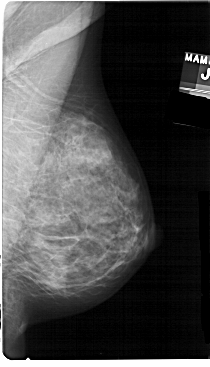

A_1392_1.LEFT_MLO

LEFT_MLO LINES 5491 PIXELS_PER_LINE 2776 BITS_PER_PIXEL 12 RESOLUTION 43.5 OVERLAY